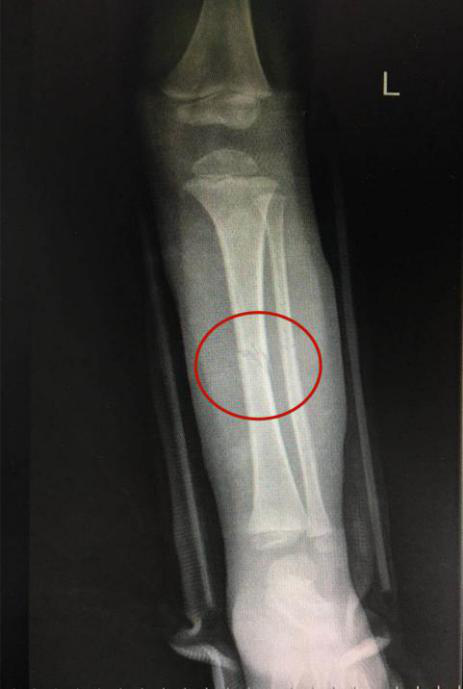

接診的瀘州市中醫(yī)醫(yī)院骨傷一科副主任中醫(yī)師李孟澤查看了患兒之前的X光片及左下肢情況,發(fā)現(xiàn)其骨折移位較大(骨折處彎曲呈30度角以上),導(dǎo)致左下肢中段嚴(yán)重畸形。

復(fù)位后,經(jīng)再次照X光顯示,患兒左下肢脛腓骨斷端緊密對(duì)合,外觀畸形得以糾正,手法復(fù)位治療非常成功。

手法復(fù)位前X片顯示脛腓骨斷端,左下肢中段嚴(yán)重畸形

手法復(fù)位后X片顯示脛腓骨斷端嚴(yán)密對(duì)合,左下肢中段畸形糾正